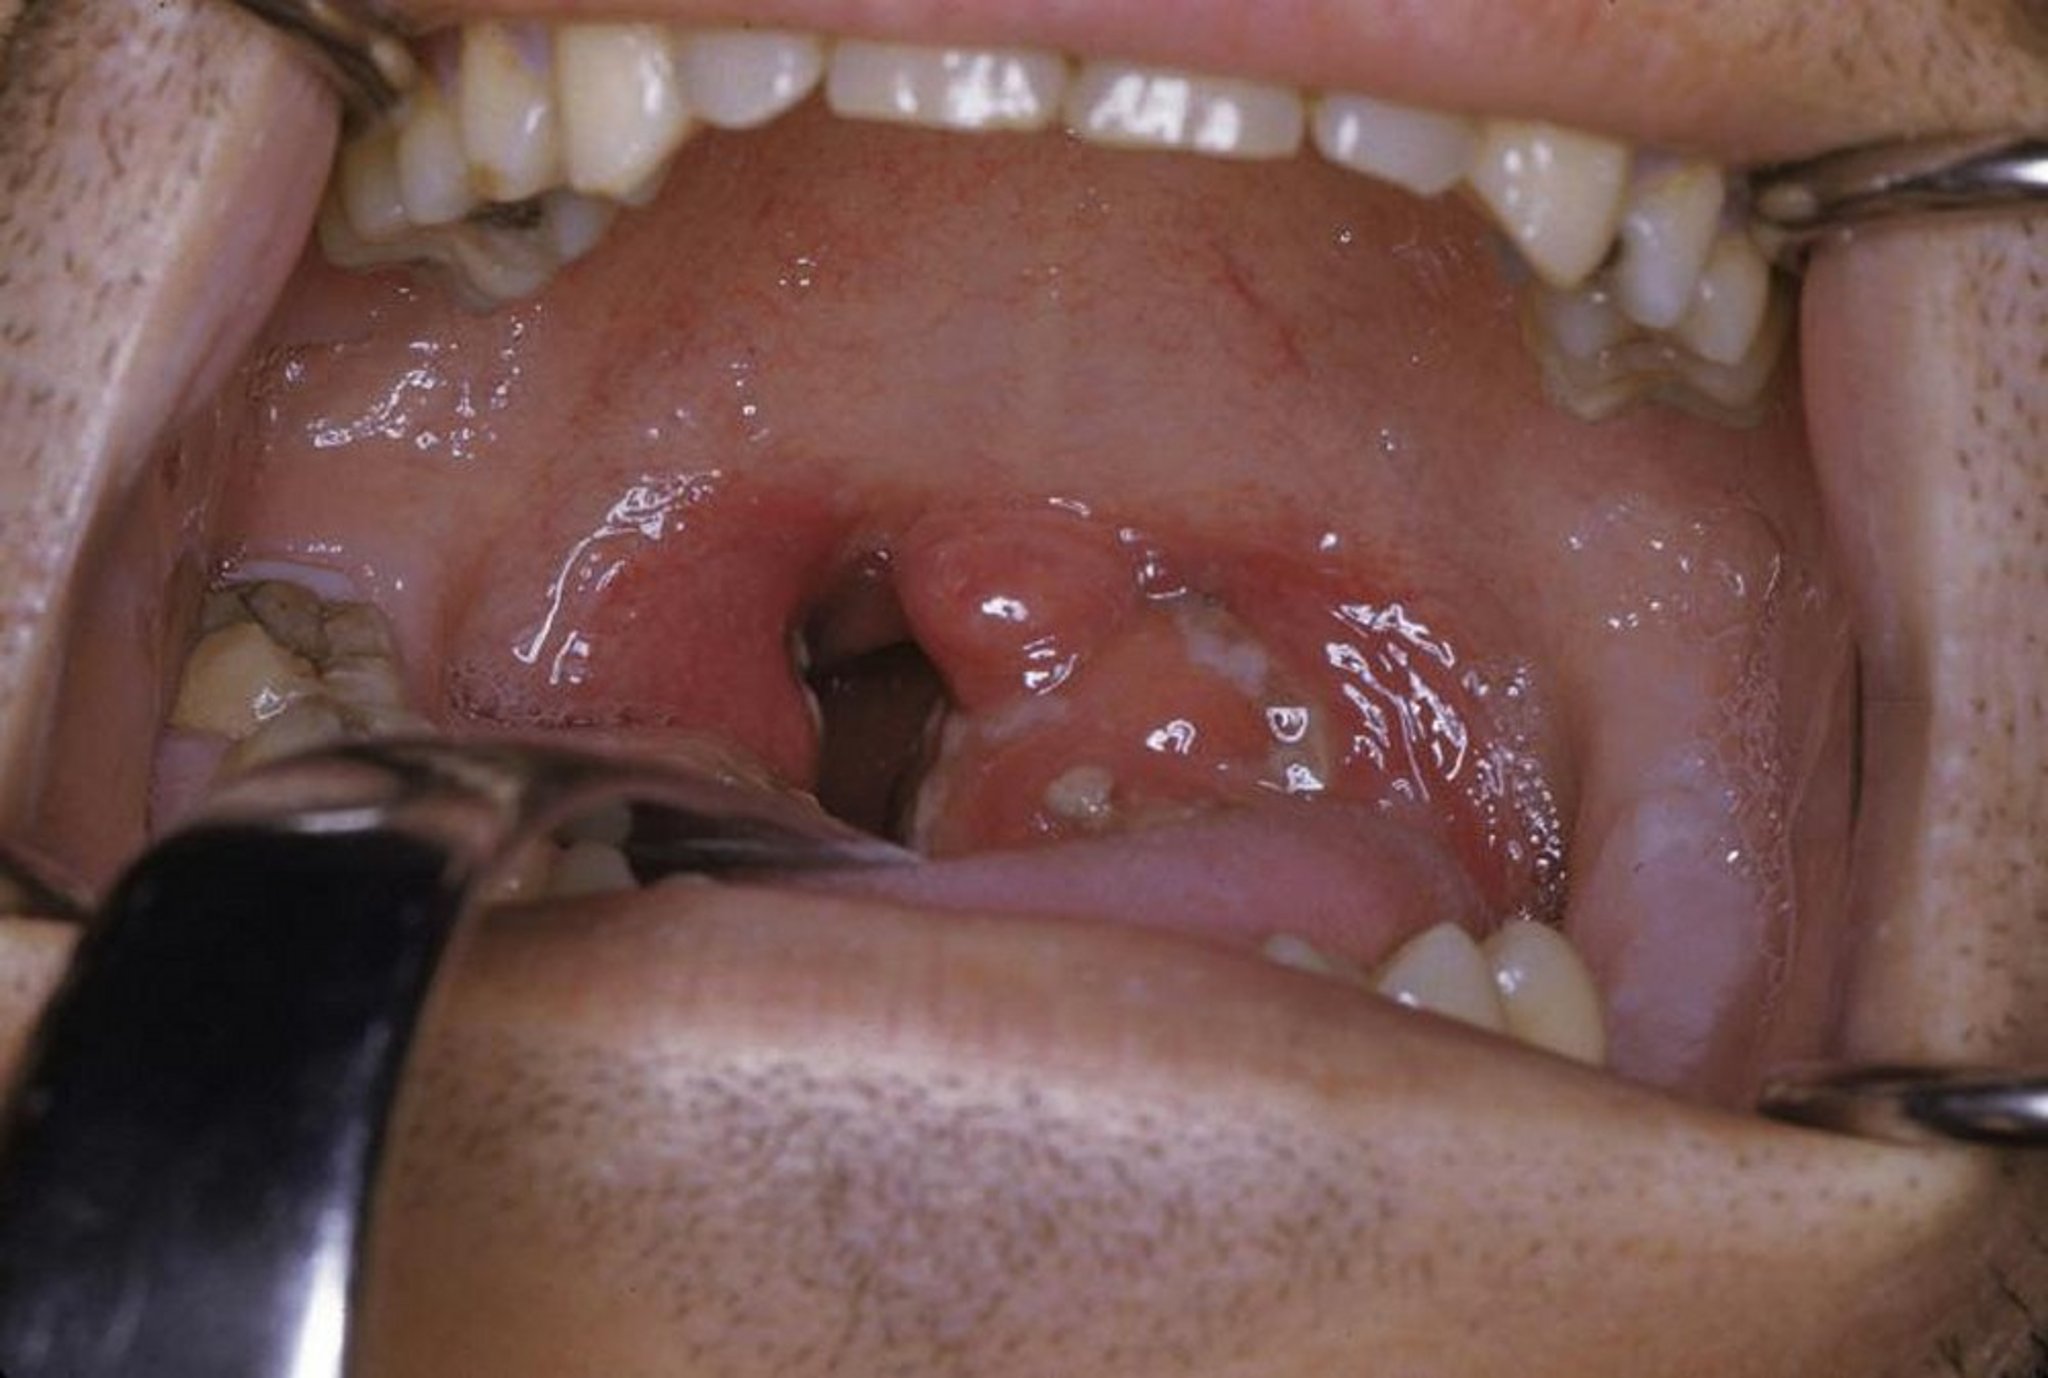

This photo shows acute tonsillitis with exudate and erythema.

Photo provided by Clarence T. Sasaki, MD.